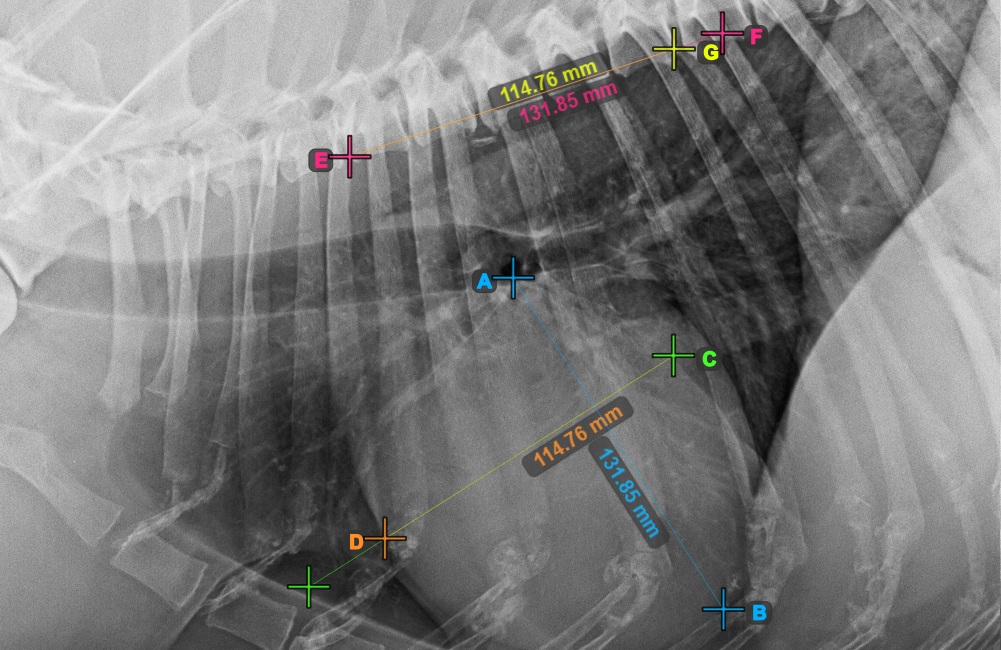

The image below represents a typical placement of the Bifurcatio tracheae point.

../../_images/image393.jpg